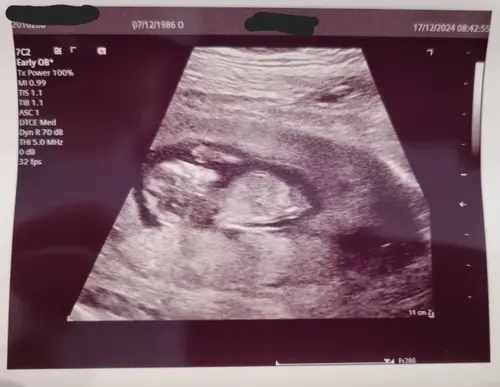

Iemand die al een gokje durft te wagen? Ben nu 11+1. Is vroeg maar er gaat niet nog een echo komen voor de 20 weken echo 😅 -edit mod Eliza- foto weggehaald op verzoek van plaatser